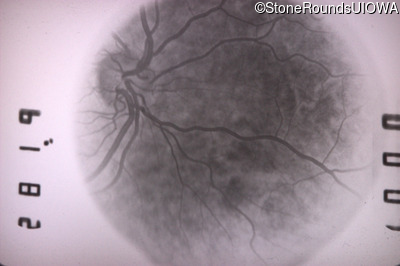

Fluorescein Angiography - Left - 20/20 -1 sc

Exemplar